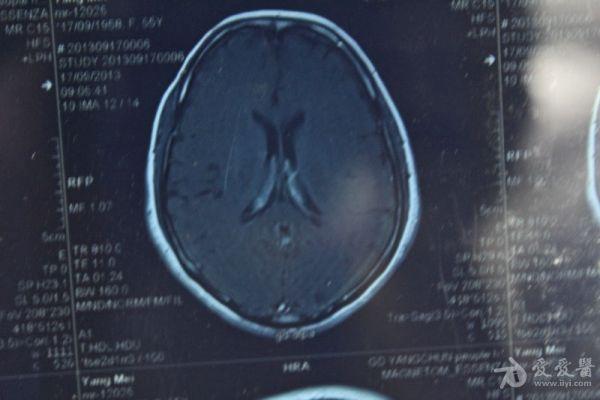

脑部占位病变CT,MRI图片,请帮忙诊断

最近感图样,无其它脑病病史

考虑脑膜瘤!!

磁共振没有平扫,增强矢状位没找到病灶。像脑膜瘤。

图片不是很清楚,应该是脑膜瘤!